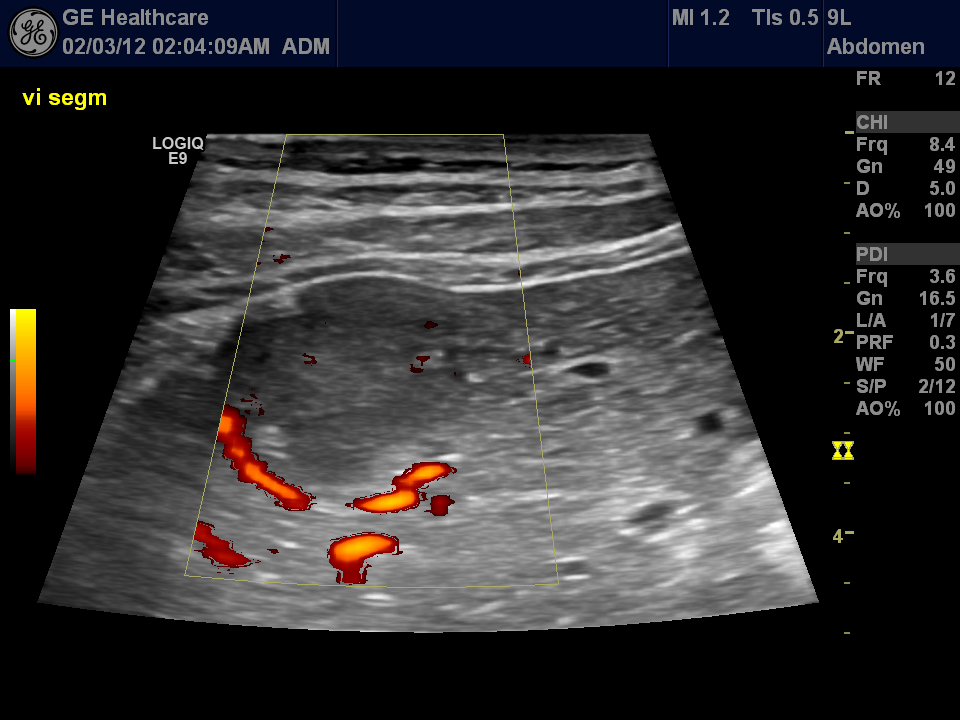

overlayed „reconstruction” of the contrast-enhancement

this technique is similar to the MIP reconstruction of CT by merging layers sonographic images